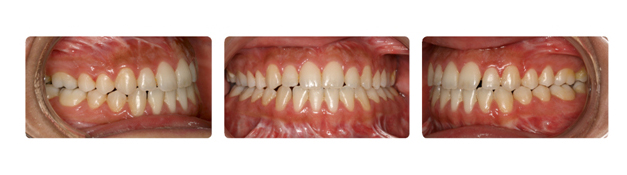

| پس از گذشت دو سال از درمان فک و دندانها مرتب شده و سر جای خود قرار گرفته اند: |

![]() |

| همچنین پس از گذشت یک سال از پایان درمان همچنان نتیجه رضایت بخش است: |